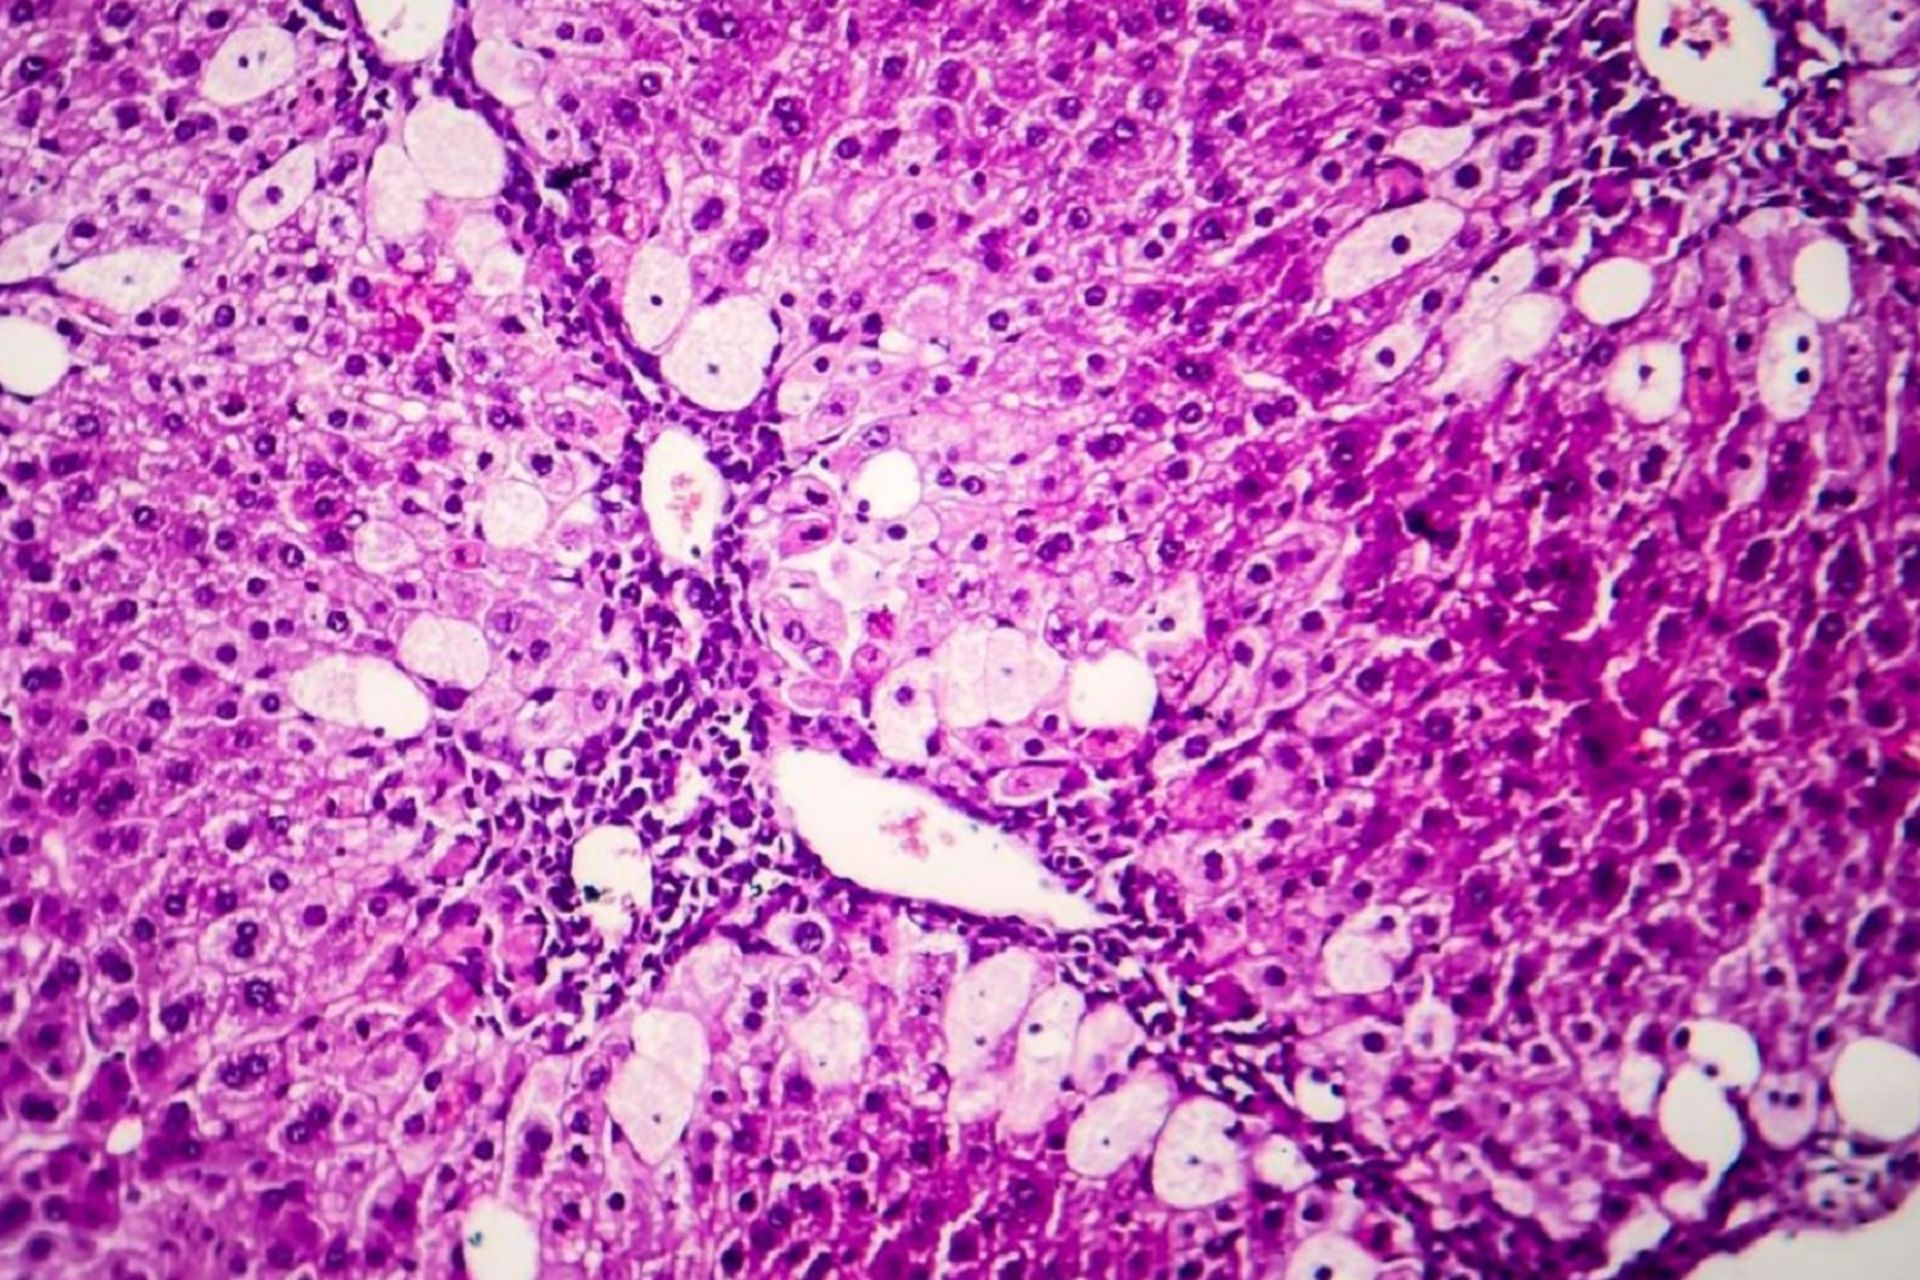

این به‌اصطلاح مطالعه، تحقیق علمی رسمی نیست؛ بلکه درواقع یک مطالعه‌ی موردی است، یعنی گزارشی در مورد وضعیت سلامتی تنها یک شخص. در این مطالعه‌ی موردی که در ژورنال هپاتولوژی در ۲۱ آوریل ۲۰۲۲ منتشر شد به بررسی وضعیت سلامت کبد یک مرد ۵۲ ساله در آلمان پرداخته شده است. فرد مورد بررسی، دو تا سه هفته پس از دریافت واکسن کووید ۱۹ از نوع واکسن mRNA فایزر به بیماری هپاتیت حاد مبتلا شد. نمونه‌برداری‌های انجام‌شده از کبد او علائم التهاب و حضور سلول‌های T را نشان می‌داد. سلول‌های T که به آن‌ها لنفوسیت تی نیز گفته می‌شود نوعی از سلول‌های دستگاه ایمنی بدن هستند.

حضور سلول‌های T در کبد قویاً نشان‌دهنده‌ی وجود التهاب در کبد این شخص است که می‌تواند ناشی از پاسخ سیستم ایمنی بدن او به واکسن کووید ۱۹ باشد. پزشکان آلمانی که احساس کردند یافته‌های آن‌ها در مورد التهاب کبد این فرد می‌تواند با هپاتیت ناشی از اختلال خودایمنی سازگار باشد او را با بودزوناید خوراکی و درنهایت با ترکیبی از استرویدها و اورسودوکسی کولیک اسید تحت‌درمان قرار دادند. درنهایت پس از گذشت هشت هفته سطح آنزیم‌های کبد این شخص به حالت عادی بازگشت.